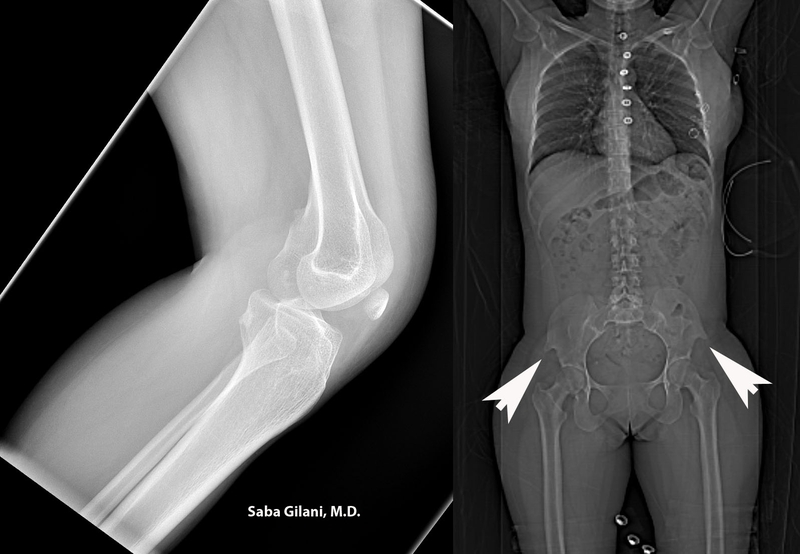

Người mắc hội chứng móng và xương bánh chè thì có móng tay và móng chân phát triển không đều. Móng tay và móng chân có thể có hoặc không, hoặc có thể có màu đục. Ngoài ra còn có các bất thường ở xương bánh chè. Trong đó có thể có xương bánh chè có thể gặp các vấn đề như: Thiểu sản hai bên, trật khớp đầu quay, không có xương bánh chè,...

Ngoài ra người bệnh còn có thể có các dấu hiệu như: Vẹo cột sống, cử động khuỷu tay hạn chế, đầu gối không vững, tăng nhãn áp, tăng huyết áp,... Các triệu chứng trên móng và xương bánh chè thể hiện rõ ngay từ khi sinh ra. Các triệu chứng khác sẽ biểu hiện vào những năm trưởng thành.